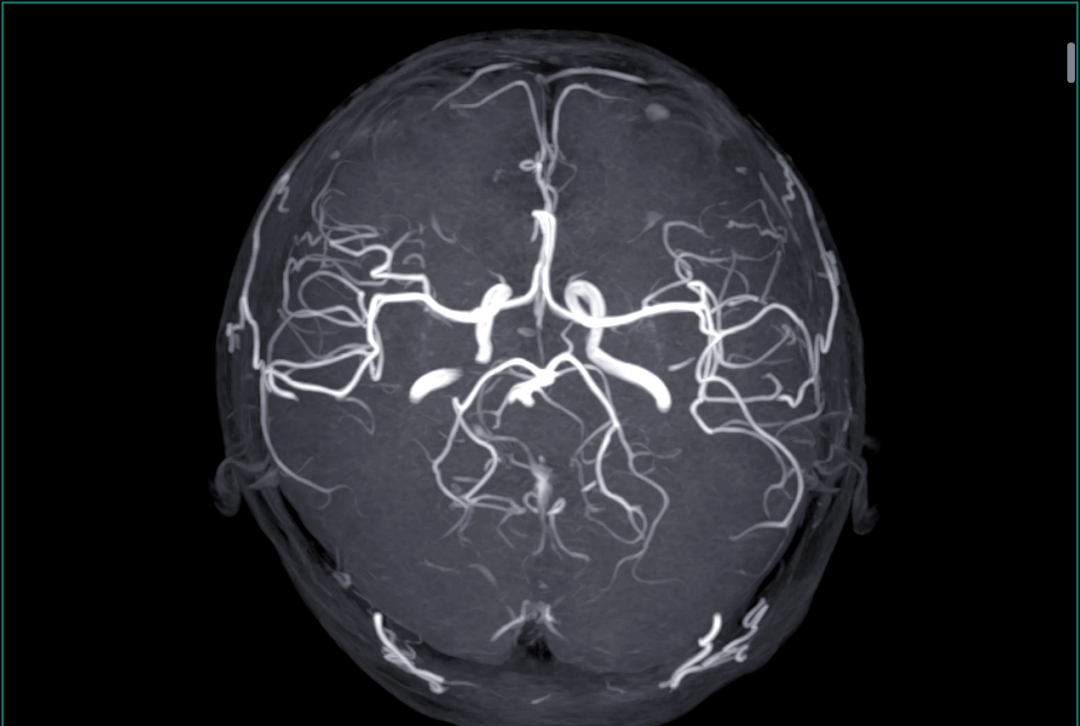

3、在磁共振设备具有强大的磁场虽然磁共振检查对人体无辐射伤害,但在磁场的作用下身体里的金属对人的伤害可不小,所以虽然核磁共振属于无损性检查,不按规矩来还是很危险的很多女士不是想隐瞒病情,故意做的,而是缺少意识,医生没问到自己就忘了说,虽然还有检查,但还是比较危险的事情,这种意外很可怕;诊断方法目前诊断脑动脉瘤的检查手段包括头颅CT头颅核磁共振MRI头颅CT血管成像CTA全脑血管造影DSA等治疗方法脑动脉瘤在明确诊断之后,应尽早治疗治疗方法分为开颅手术和介入栓塞两种开颅手术的动脉瘤夹闭术是治疗普通脑动脉瘤最常用的治疗手段,优点在于疗效直观医疗费用少;打开腾讯新闻,查看更多图片 据了解,就在近期就有一群实习生工作中疏于职守,将一男子遗忘在检查舱内长达二十分钟这到底是怎么一回事根据相关媒体在近日的报道得知有一位68岁的老先生去周口的一家医院做检查,其中有一项是核磁共振检查在做完检查之后,老先生一直在等待工作人员带自己出来,可是没有人管他,他只能一直待在检查舱内。